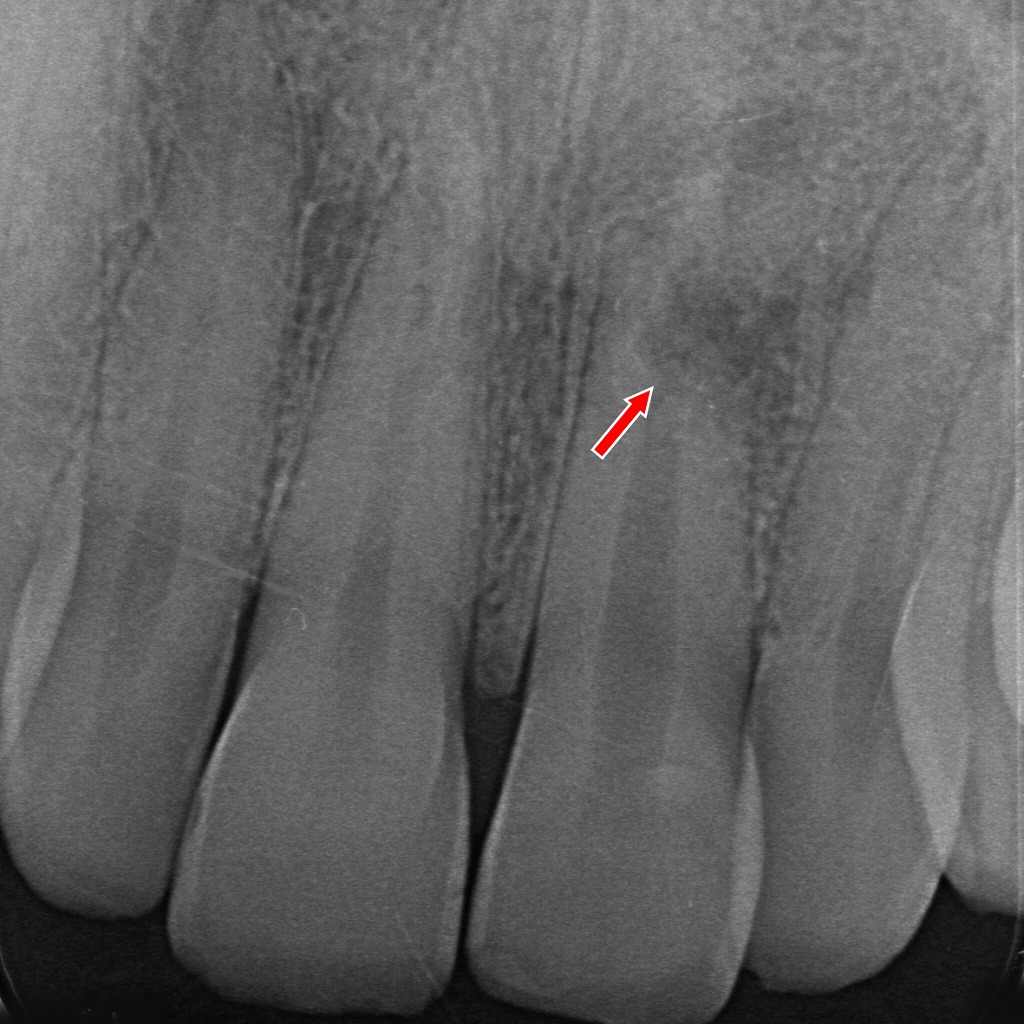

📌 画像の解説:病的歯根吸収の根充後・経過観察

矢印で示された部位には、外部吸収(external resorption)によって生じた不規則な透過像が依然として認められます。これは、歯根外側の歯質が溶けた部分を示す典型的な像です。

一方、根管内部には根充材が均一に充填されており、根管の封鎖は良好です。再感染リスクを最小限に抑えた状態が維持されていると判断できます。

✔ 経過観察時のポイント

- 吸収部の透過像はすぐには消失しない

外部吸収は骨や歯根膜の再生とともに徐々に変化するため、複数ヶ月~年単位の観察が必要です。 - 根充材の位置は安定しており、内部からの感染源は遮断されている

治療としては適切に封鎖されている状態。 - 新たな拡大や境界不明瞭化がないかが観察上の重要点

今回の画像では、

👉 吸収部は残存しているものの、病変の拡大を示唆する所見は乏しく、根管治療後としては良好な経過が期待できる状態

と評価できます。